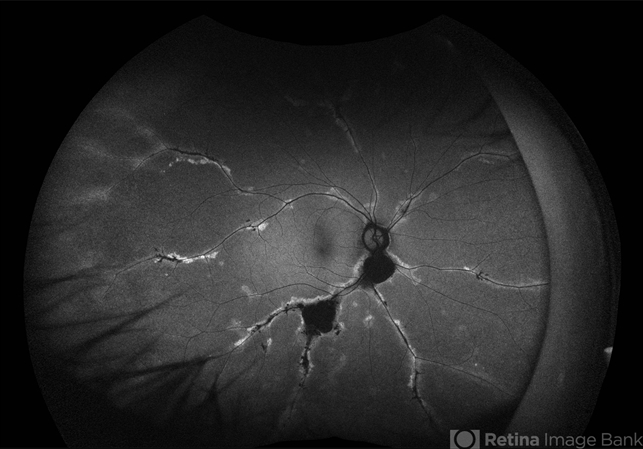

- pigmented paravenous chorioretinal atrophy (PPCRA)

- Fundus Autofluorescence Image of a 42YO female patient diagnosed with Pigmented Paravenous Retinochoroidal Atrophy. Findings were bilateral. Image shows hypoautofluorescence in the affected areas due to overall loss of RPE cells and thus lower lipofuscin levels.